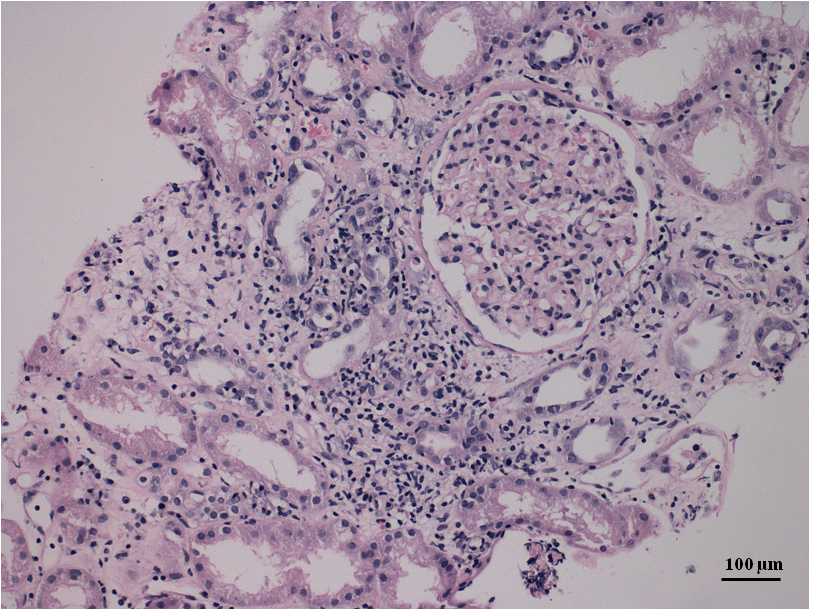

In this paper, we present a newly developed acute humoral and cellular rejection with acute allograft failure and need of haemodialysis 14 days after administration of the adenovirus vectored SARS-CoV-2 vaccine (AstraZeneca; CHADOx1, AZD1222). This occurred in a patient who previously had an asymptomatic COVID-19 infection.